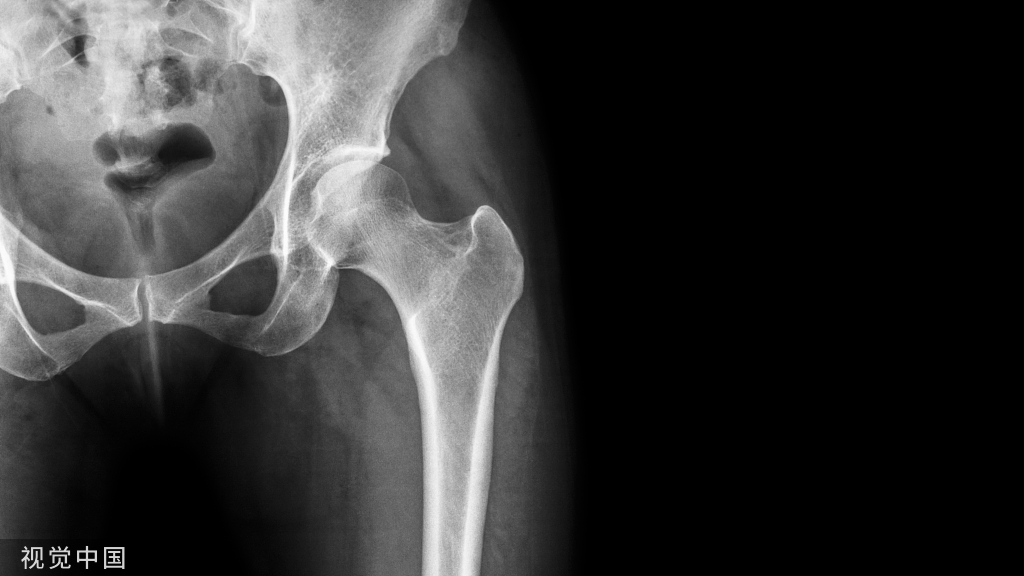

临床上 ,有较多车祸 、高处摔伤等高能量外力引起的胫腓骨、尺桡骨以及肱骨髁上骨折的闭合性损伤以及 直接暴力性损伤尤其是挤压伤 ,常常引起较重的软组织损伤 ,容易引发张力性水泡。